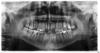

zet Опубликовано 25 февраля, 2009 Автор Поделиться Опубликовано 25 февраля, 2009 (изменено) панорамный снимок.серебряных штифтов раньше было больше, но один зачем-то вытащили при осмотре. Дорогое сейчас серебро? Изменено 25 февраля, 2009 пользователем zet Ссылка на комментарий

Bier Опубликовано 25 февраля, 2009 Поделиться Опубликовано 25 февраля, 2009 зубы однозначно удалять. Серебрянные штифты вынули и выбросили мне больше нравится вариант №4.2 или 4 имплантата (надо уже думать и решать на модели) с одномоментной нагрузкой временными коронками.Если сразу поставить постоянные, то когда десна изменит свой контур, будет некрасиво. Ссылка на комментарий